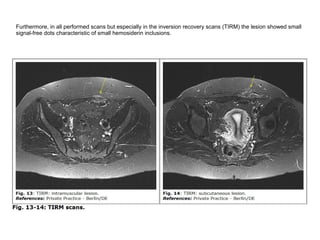

Furthermore, in all performed scans but especially in the inversion recovery scans (TIRM) the lesion showed small

signal-free dots characteristic of small hemosiderin inclusions.